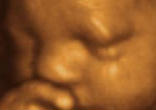

Oklahoma's Ultrasound Law: Is Medical Information Unwanted Speech When Abortion is Involved?

Opponents of a new law in Oklahoma say that requiring Doctors to convey ultrasound information to patients is "compelling doctors ... continue reading